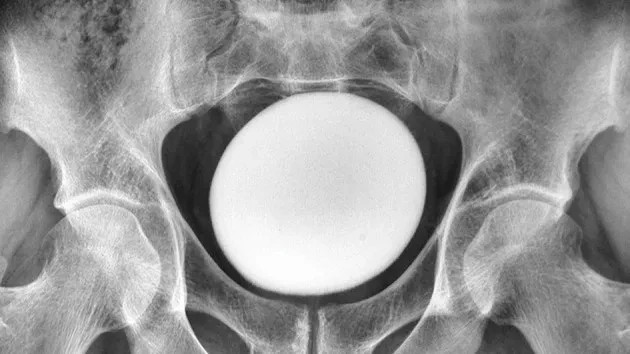

Saat dilakukan pemeriksaan fisik pada bagian perut, dokter meraba adanya massa besar, halus, dan padat di atas tulang pubis, bagian depan panggul tempat kedua tulang kemaluan bertemu.

Massa padat tersebut tidak menempel pada tulang panggul maupun dinding perut. Pemeriksaan USG kemudian menunjukkan bahwa benda tersebut berbentuk menyerupai telur dengan diameter sekitar 11 sentimeter. Temuan ini dilaporkan dalam laporan kasus medis di NCBI.

Batu yang berhasil diangkat memiliki berat sekitar 826 gram. Ukurannya mencapai sekitar 13 sentimeter panjang, 10 sentimeter lebar, dan 8 sentimeter tinggi.